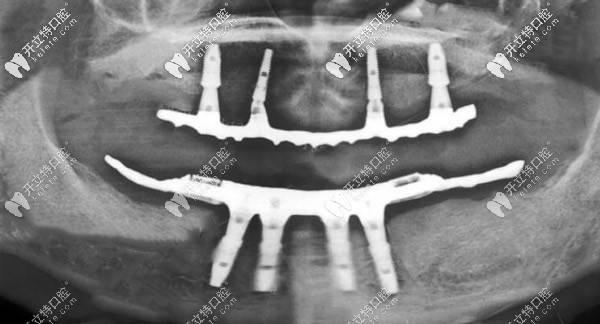

CBCT線片圖▼

ALL-ON-4種植X線片

從種完牙的圖片可以看出,種植假牙比有的真牙還要好看,當然種植牙的咬合力也是比較逼近自然牙齒的,而且有了種植體的支撐可以有效緩解牙齦的吸收。